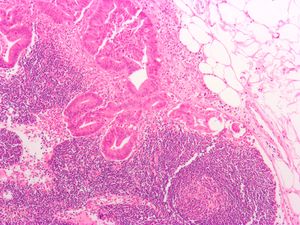

علم الأمراض